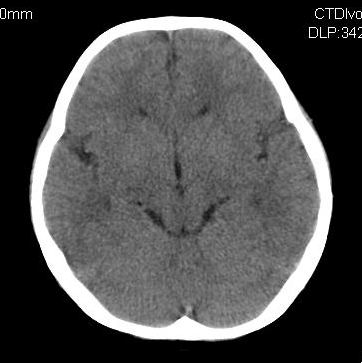

女,10岁,智力发育不良,既往史无特殊。

脑裂畸形,灰质异位